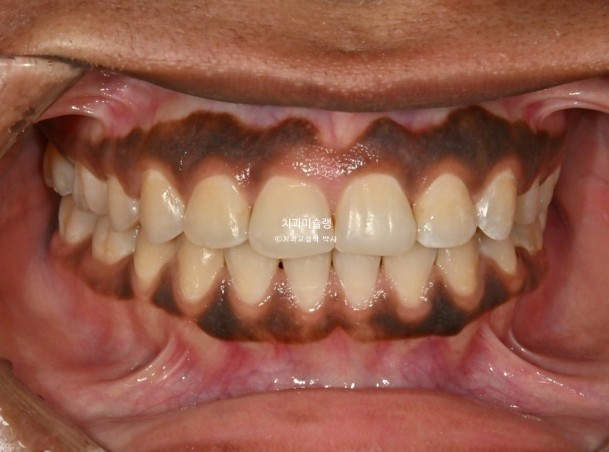

At 2 years into treatment, closure of the extraction spaces was completed.

At this stage, the implant fixture was first placed in the mandibular posterior region, followed by intrusion of the supra-erupted opposing tooth.

After successful intrusion of the opposing tooth, the implant crown was delivered in December 2025, and the orthodontic treatment was completed.

The total treatment period was 2 years and 5 months.

The maxillary and mandibular midlines are well aligned,

and the molar occlusion demonstrates a tight Class I relationship with no spacing.We will now review the before-and-after comparison.

The treatment, including implant placement, was completed with a clean and stable result.